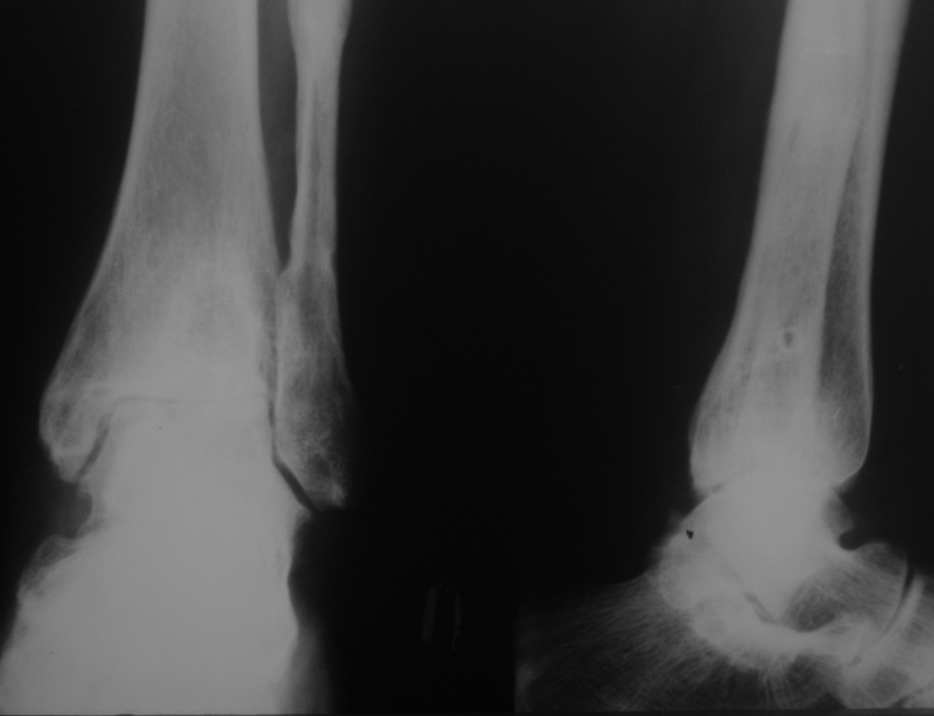

Уважаемые коллеги, разъясните ситуацию.Пациентка, 45лет. 9 месяцев назад произведен синтездвухлодыжечного перелома правой голени.

Конструкции на данный момент удалены. Объем движений на фото. Сейчас беспокоят скованость в области сустава, боли к концу рабочего дня - классическая клиника артроза.Пропила 4 курса найз. Откуда артроз такой выраженности (на рентгенограмме)? Поможет ли консервативное лечение и какое поможет наверняка?

Артроз, во-первых, вследствие неконгруентности суставных поверхностей - имеется укорочение малоберцовой кости; во-вторых имеется синостозирование берцовых костей (вместо тугоэластисчного синдесмоза).

>Артроз, во-первых, вследствие неконгруентности суставных поверхностей - имеется укорочение малоберцовой

Но укорочение - 3мм, и потом суставная поверхность наружной лодыжки не несет осевой нагрузки

>во-вторых имеется синостозирование берцовых костей (вместо тугоэластисчного синдесмоза).

Даже если это были оригинальные имлантаты "Synthes", то к "АО" этот остеосинтез не имеет ни какого отношения. Потому, что вся философия АО в отношении переломов лодыжек основана на том, что наружная лодыжка это нагружаемая часть сустава, на которую приходится примерно 1\6 веса тела. Восстановление длины м\б кости является приоритетным, и наружную лодыжку называют ключом г\ст сустава.

"Стягивающий винт на синдесмоз" противоречит АО, т.к. этот винт должен быть позиционным и не должен создавать компрессиию на уровне сочленения берцовых костей и между наружной лодыжкой и таранной костью. Стягивающий винт - основная причина синостоза на месте синдесмоза.

Не, не помогут. Есть показания к назначению (заметьте не лечению, а именно назначению!) протеза синовиальной жидкости и всяких "хондропротекторов" - это начальные стадии артроза. В обсуждаемом наблюдении артроз 3 ст.